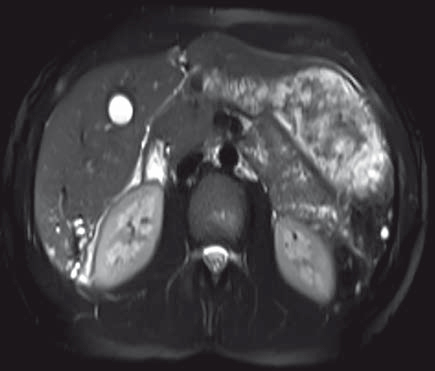

Figure 5 : IRM hépatique, coupe axiale T2 avec saturation de la graisse

Description de l'IRM hépatique

• Multiples petits kystes confluents en hypersignal T2, hyposignal T1, de paroi fine se rehaussant après injection de produit de contraste.

• De siège intra-hépatique (segment VI), sur foie sain.